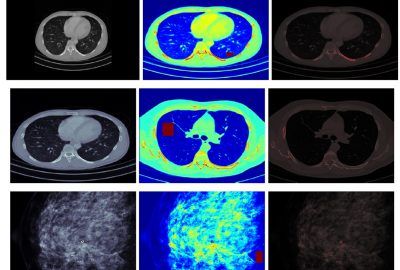

The luminance range of the sun to the night sky is approximately 14 orders of magnitude. Current display technology can present approximately three orders of magnitude, however this number is increasing as High-Dynamic-Range (HDR) technology develops to further emulate reality [Seetzen et al. 2004]. Another benefit to HDR technology is the increased bit-depth enabling the display of more information. However, a major limitation in the perception of added bit-depth is veiling glare. The increased luminance range in HDR displays have the ability to produce glare sources that can reduce the visible contrast in neighboring dark areas. This effect is especially undesirable in the visualization of scientific data and in medical images. The HDR presentation must be optimized so that the benefits of a wide luminance range are not diminished by glare in the human visual system. One important question is, what is the largest luminance range that avoids these veiling glare effects while presenting the most bit-depth? We have found that the answer is highly dependent on the spatial and luminance distribution in the image. Many models have been proposed to estimate the veiling glare in a given image. A well known model is High-Dynamic-Range Visual Difference Predictor 2 (HDR-VDP-2) [Mantiuk et al. 2011], a calibrated method able to determine the visibility of differences in HDR images. Building on a number of previous metrics of visible difference, this model operates in a broad range of viewing conditions, from scotopic to photopic vision. More importantly, HDR-VDP-2 can be used to represent the effects of visual glare in signal detection. The inputs of the HDR-VDP-2 are a luminance map of an image, a reference image, and an image with the target. The software outputs the probability of target detection accounting for various visual effects including veiling glare.